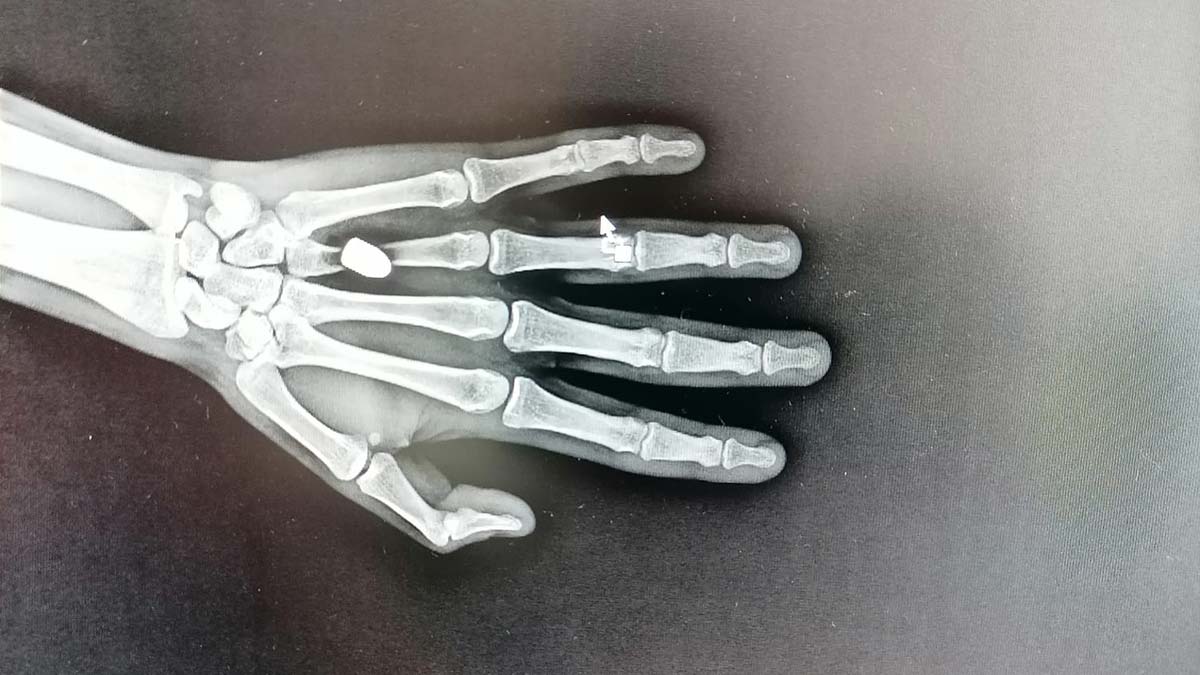

Özellikle Trabzonspor’un geçen sezon şampiyonluğu ve sonrasında alınan güvenlik önlemleri ile olumlu sonuç veren ‘Mutluluğa kurşun sıkmayın’ kampanyasından yaklaşık 5 ay sonra kentte ilk kez yorgun mermi vakası yaşandı. Sürmene ilçesi Çarşı Mahallesi’nde 22 Ağustos’ta otobüs durağında beklediği sırada elinde aniden acı hisseden Mehmet İskender, sol avucunun kanadığını fark etti. Kanı arkadaşının yardımıyla temizleyen İskender, Sürmene Devlet Hastanesi’ne gitti. Tedaviye alınan İskender’e çekilen röntgende, avucuna yorgun merminin saplandığı tespit edildi. Mermi çekirdeği elinden ameliyatla alınan İskender, taburcu edildi. Polis ekipleri, olayla ilgili inceleme başlattı.

Sürmene Devlet Hastanesi Başhekimi Osman Yoloğlu, röntgen filminde mermi tespit ettiklerini belirterek, “Elinde ağrı hissettiğini söyleyen hastamızın elinde de bir yarası vardı. Yaptığımız tetkikler sonrası elinde, mermi çekirdeği olduğunu tespit ettik. Hastamızı hemen ameliyata aldık ve elinden mermi çekirdeğini çıkarttık. Durumu, çok şükür iyi” diye konuştu.